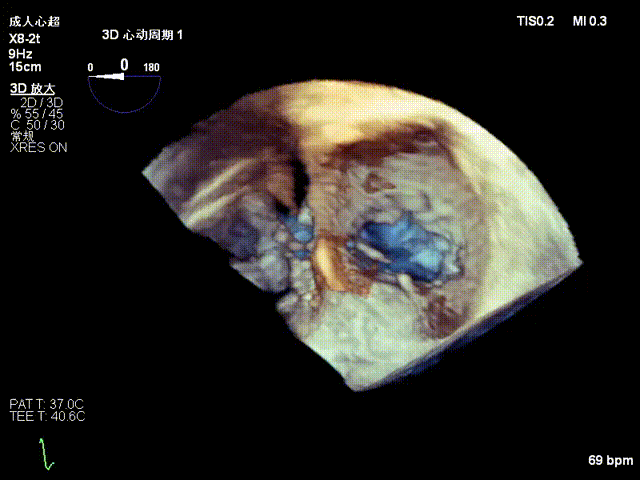

2.Annuloplasty Effect: Annular morphology remodeled, central gap significantly reduced.

Preoperative 3D

Postoperative 3D